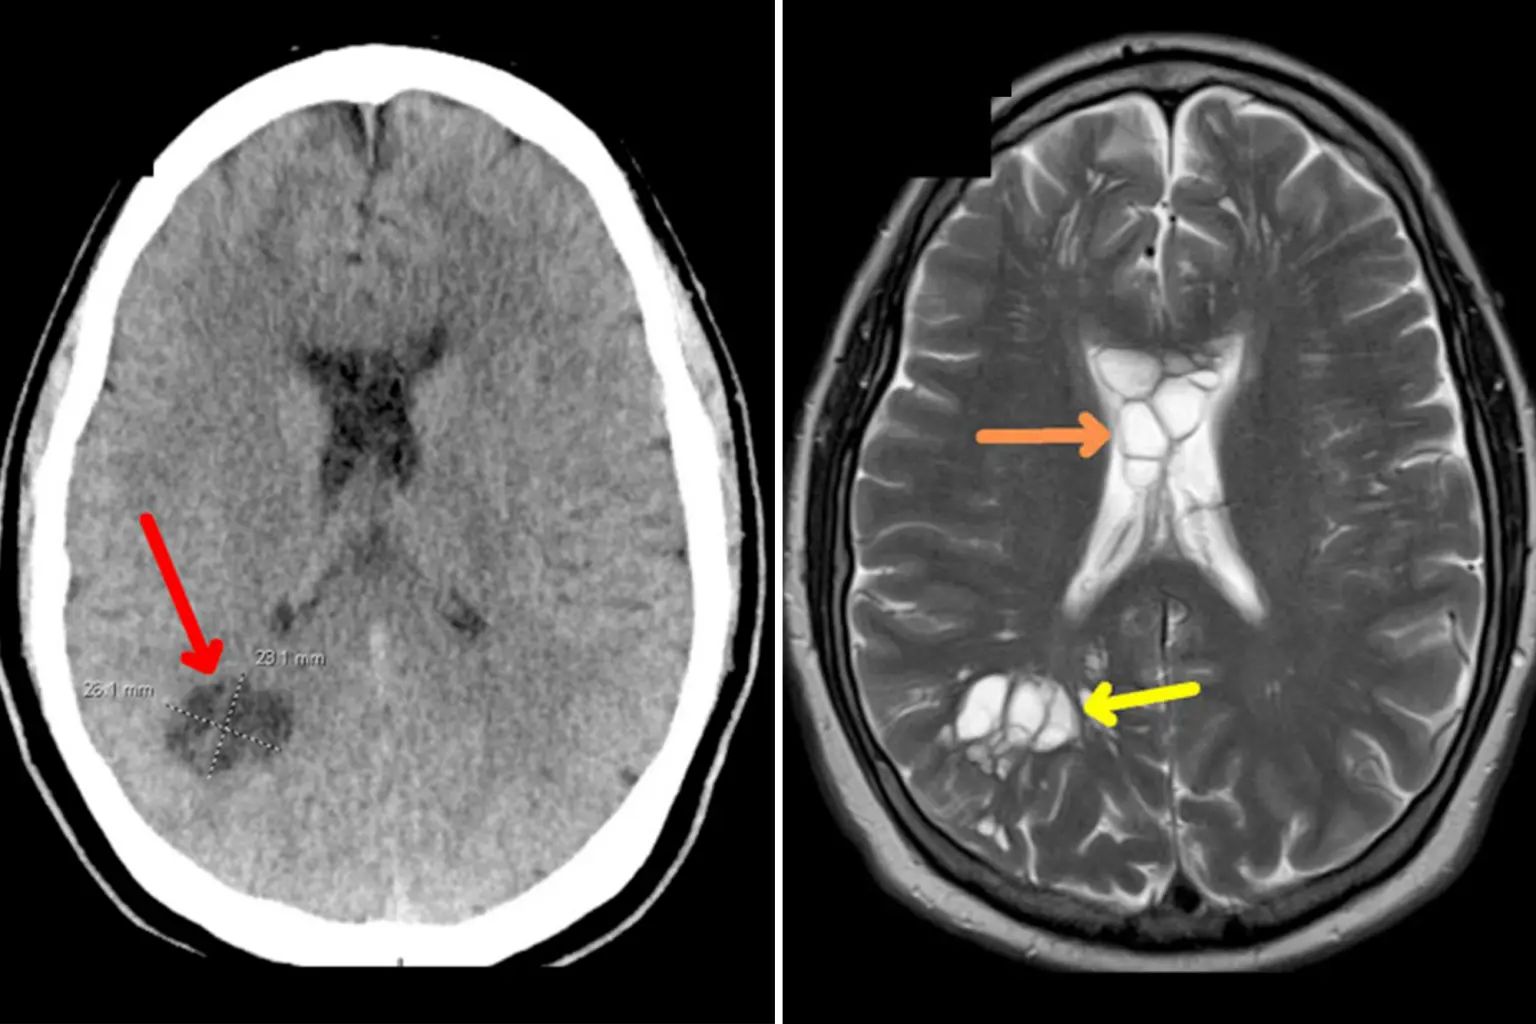

11 มีนาคม 2567 นิวยอร์กโพสต์ รายงาน กรณีชายชาวออร์แลนโดจากรัฐฟลอริดาวัย 52 ปี ที่คิดว่ากำลังป่วยเป็นโรคไมเกรนขั้นรุนแรง ที่จริงแล้วกำลังต่อสู้กับพยาธิตัวตืดในสมอง วารสารกรณีทางการแพทย์อเมริกัน รายงาน ผู้ป่วยนิรนามรายนี้ได้ไปพบแพทย์หลังจากอาการปวดหัวเรื้อรังนานร่วมสัปดาห์ในตลอดระยะเวลาสี่เดือน ผลการสแกนเผยให้เห็น ซีสต์ในสมองทั้งสองซีกของเขา เช่นเดียวกับอาการบวม ซึ่งผู้เชี่ยวชาญด้านโรคติดเชื้อยืนยันว่าเป็นผลมาจากพยาธิตืดหมูที่วางไข่ในสมองของเขา และระคายเคืองเนื้อเยื่อใต้กะโหลกศีรษะ

ดังนั้น ผู้ป่วยได้รับการวินิจฉัยว่าติดเชื้อปรสิต Neurocysticercosis ซึ่งเป็นศัพท์ทางวิทยาศาสตร์สำหรับปรสิตที่วางไข่ จนกลายเป็นลักษณะก้อนคล้ายซีสต์ที่ประกอบด้วยปรสิตระยะยังไม่เจริญเต็มที่ของพยาธิตัวตืด ซึ่งแพร่เชื้อไปยังส่วนต่าง ๆ ของร่างกาย ทำให้เกิดการอักเสบ